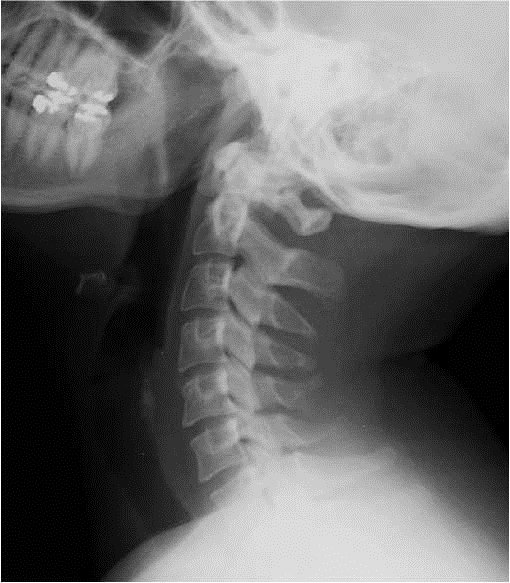

IMAGE NORMALE

FRACTURE DE L’EPINEUSE DE C1

ENTORSE CERVICALE (Inversion de la courbure physiologique)